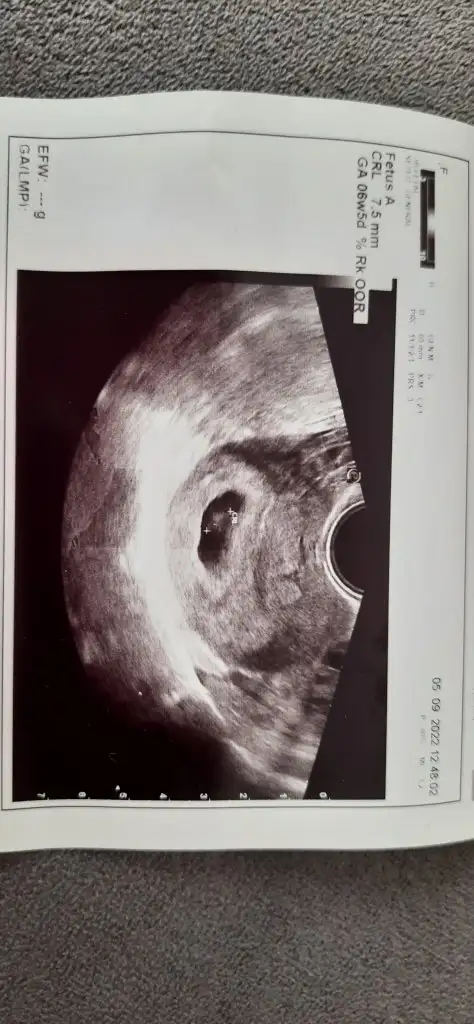

Kızlaarr geldim ben. Karından göremedi bebeği baya uğraştı ödüm koptu bir terslik var diye. Rahmin geride göremiyorum Alttan bakacağım dedi o çok korktuğum doğum masasına nasıl çıktım anlamadım bile umrumda olmadı valla. Baya da orada baktı baktı bebeği gördük şükür makina bozukmuş kalp atışını duyamadım ama kalbi atmaya başlamış dedi gösterdi. Duyamadığım için bir burukluk oluştu ama çok şükür atıyormuş yani. Bu da ultrason😊

Çok teşekkür ederim 🤗 bebeğin boyu crl yazan yer mi acaba 7.5 mm yazıyor. Eğer öyleyse küçük mü 7+3 haftaya göre. Çünkü uygulamalarda 1küsür cm diye gösteriyor bu haftaları

Evet crl yazan yer bebeğin boyu. Belki sata göre biraz geridedir birkaç gün canım onu bilemiyorum. Aslında doktor ölçüm yaptığında ultrasona göre kaç haftalıksın yazıyo olması lazımdı. Çok fark yoktur ama, birkaç gün önde ya da geride çıkabiliyolar genelde

Adet tarihinle uyumlu dedi de bir yere de yazmamış. Biraz gelişigüzel bakıyor sorulara cevap vermiyor zaten. Neyse ben gönlümü ferah tutayım 🤗